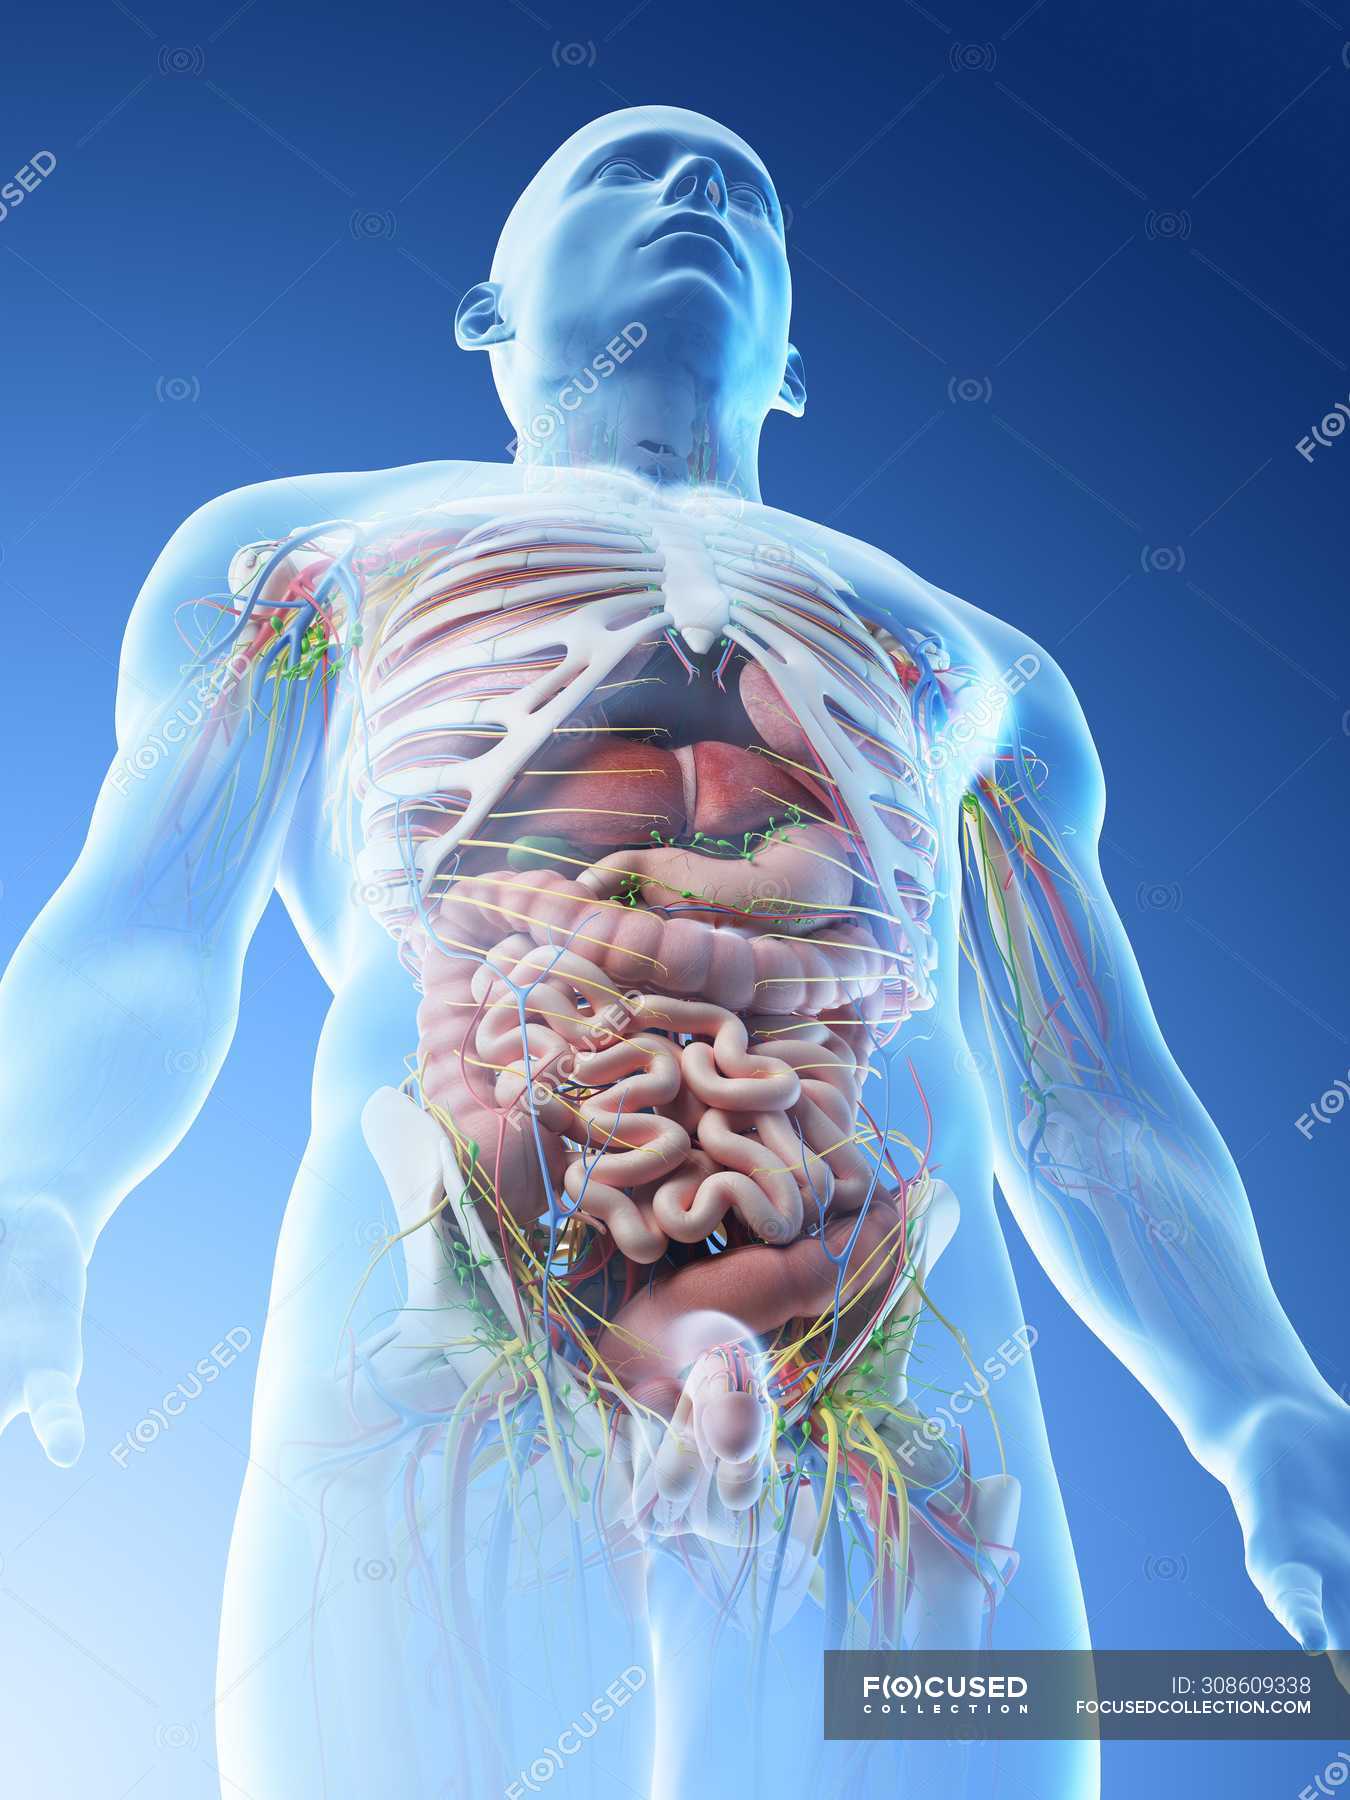

Transparent Body Model Showing Male Anatomy And Internal Organs

https://st.focusedcollection.com/13422768/i/1800/focused_308618896-stock-photo-transparent-body-model-showing-male.jpg

Male Organ Location Diagram

https://st.focusedcollection.com/13422768/i/1800/focused_308609338-stock-photo-male-upper-body-anatomy-internal.jpg

Male Organ Location Diagram